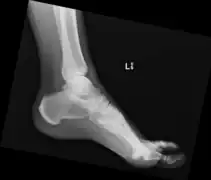

Ectopic calcification and new bone formation in diffuse idiopathic skeletal hyperostosis (DISH)

In some, the x-ray findings may correspond to symptoms of back stiffness with flexion/extension or with mild back pain.[2] Back pain or stiffness may be worse in the morning.[4] Rarely, large anterior cervical spine osteophytes may affect the esophagus or the larynx and cause pain, difficulty swallowing[5][6] or even dyspnea.[7] Similar calcification and ossification may be seen at peripheral entheseal sites, including the shoulder, iliac crest, ischial tuberosity, trochanters of the hip, tibial tuberosities, patellae, and bones of the hands and/or feet.[6]